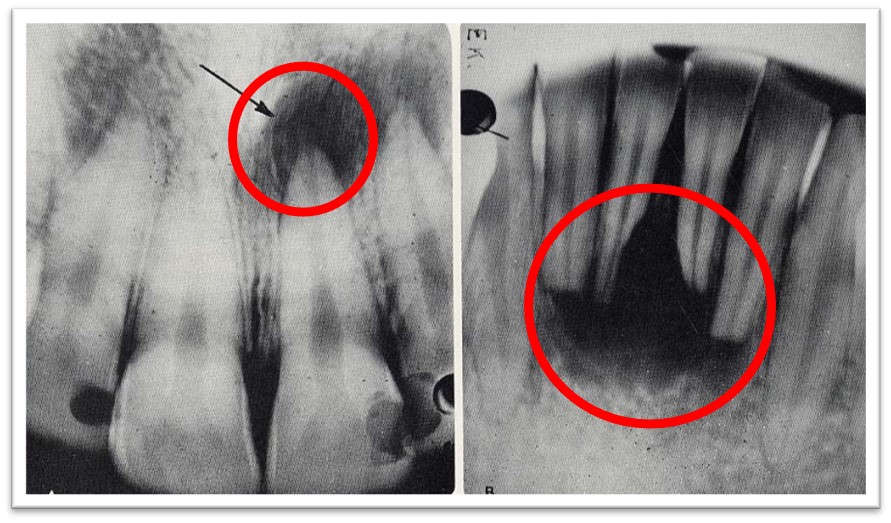

2. X线:根尖区牙周间隙增宽,或界限清楚的圆形透射影(图9.2-1)。

图9.2-1 根尖周肉芽肿X线

4. X线:根尖周有边界模糊的不规则透射影,其周围骨质疏松呈云雾状(图9.2-4)。

图9.2-4 根尖周脓肿X线